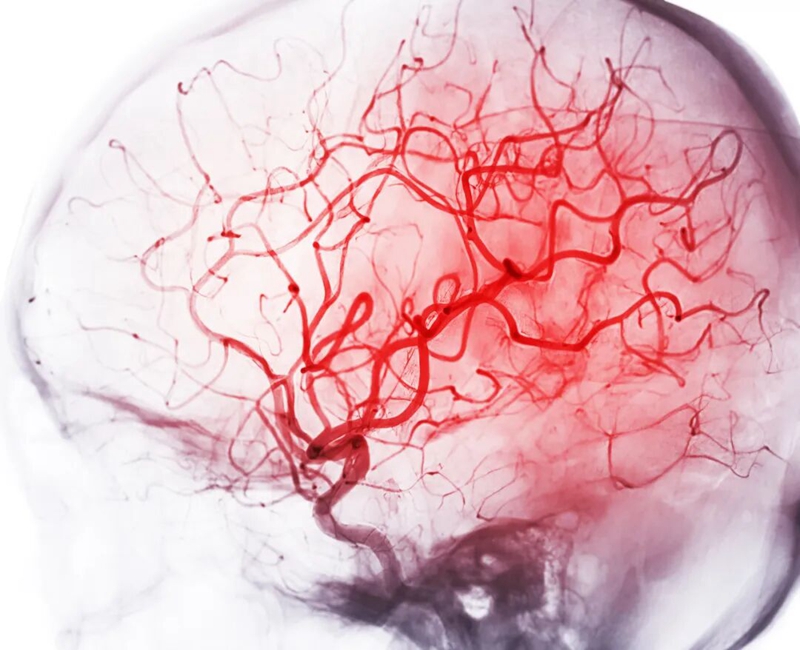

曾经被认为是“老年病”的脑出血,如今正将魔爪伸向风华正茂的年轻人。而悲剧的源头,大多指向同一个被忽视的警告——高血压。

瞬间崩盘 当高血压引爆脑出血

脑出血,俗称“脑溢血”,是高血压最严重、最致命的并发症之一。高压的血液瞬间涌出,像洪水一样挤压、摧毁着娇嫩的脑组织。这就是脑出血。它来势凶猛,致死率、致残率极高。幸存者往往面临偏瘫、失语、认知障碍等严重后果,个人生活无法自理,整个家庭也随之坠入深渊。

那个你自以为“没事”的高血压,正是在你大脑中埋下的一颗不定时炸弹。